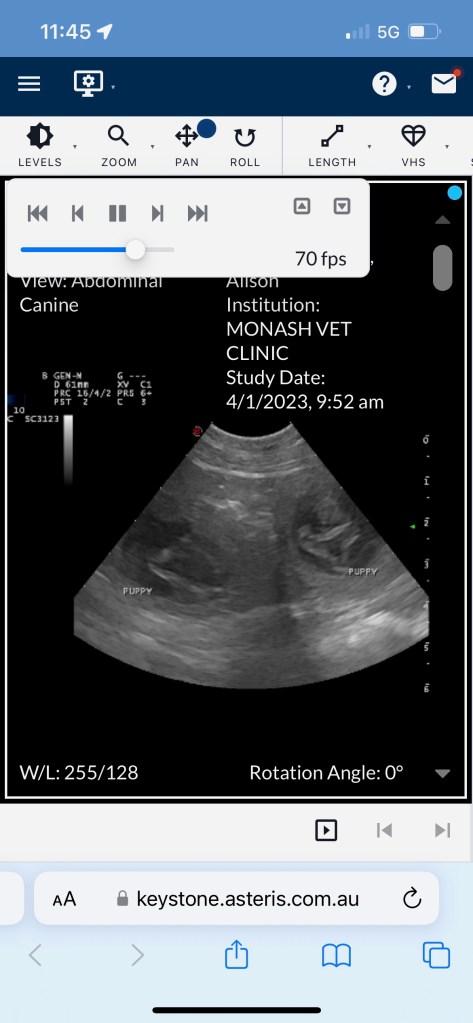

X-ray day! We can see 8 puppies! It’s possible there’s another one tucked in there but we’ll know for certain in a very short time.

Pippa is expecting! We are thrilled to announce that Pippa (Papoulab Astrea), one of Poppy’s daughters from her second pregnancy is expecting an all yellow litter of puppies, as confirmed by ultrasound. Due date is approximately 6 February.